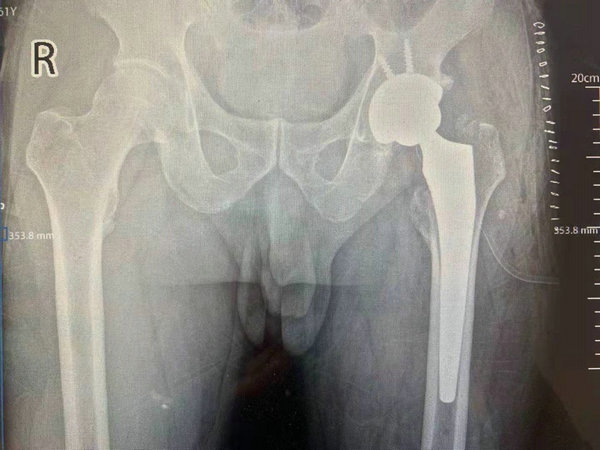

术后影像检查